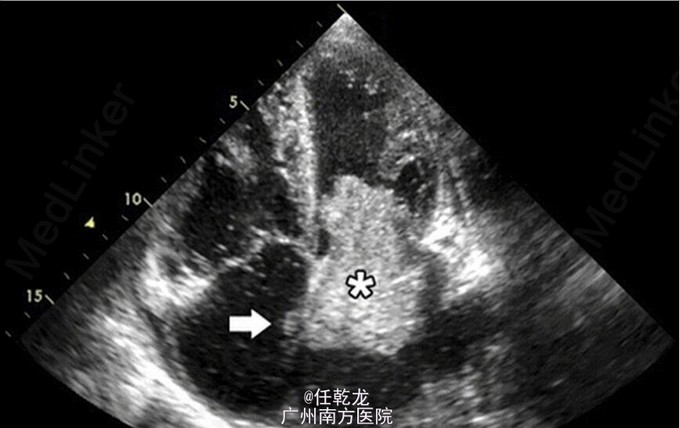

查体:生命体征平稳,心尖部闻及3/6级隆隆样舒张期杂音。其余心肺及腹部查体未见明显异常。 辅助检查:血常规、生化、肝肾功能、电解质等均未见明显异常。胸部强化 CT 显示左下叶段动脉栓塞。还显示左房内有块状物。下肢静脉超声检查结果正常。经胸超声示左房内有一大质硬物(7×5×5cm),部分占据二尖瓣口,造成“动态”的二尖瓣狭窄,并通过一较大的 II 型房间隔缺损伸进右房。

诊断:1. 左房粘液瘤 2. 肺栓塞 患者在常规抗凝、营养心肌等对症处理后接受手术治疗。该肿物起源于房间隔左房基底部,成功将其切除。房间隔缺用心包补片封堵。病理组织学实验证实肿物为粘液瘤。术后恢复顺利。